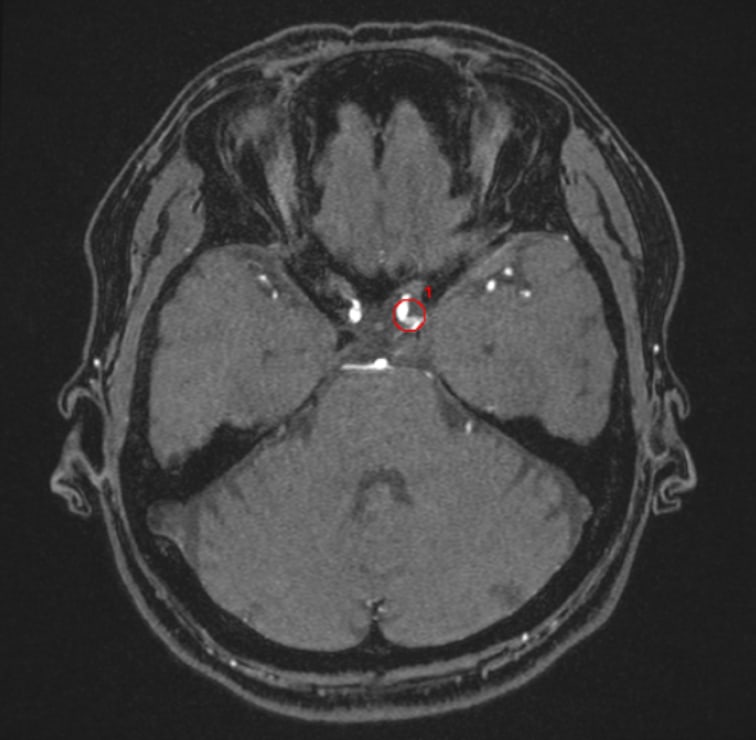

解析事例

内頚動脈-後交通動脈